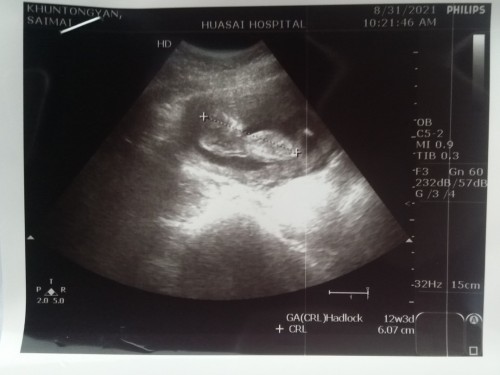

ซาวครั้งแรก12w

Post reply image